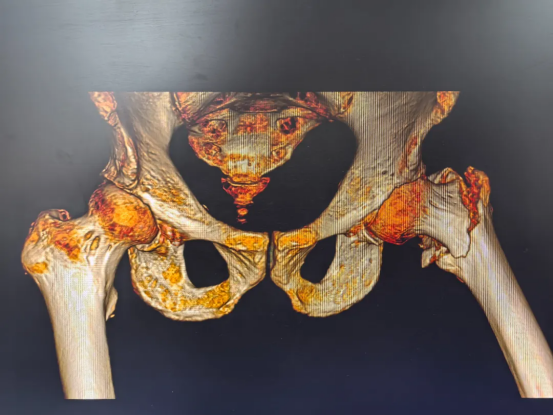

95岁的夏爷爷和80多岁的陈爷爷、王奶奶(均为化名)均因意外摔倒导致髋部剧痛、无法行走,被家人紧急送至我院骨关节科就诊。经详细检查,三位老人被诊断为“股骨粗隆间骨折”,还合并其他基础疾病。这种骨折被称为"人生最后一次骨折",对高龄患者而言尤为危险。

术前摄片